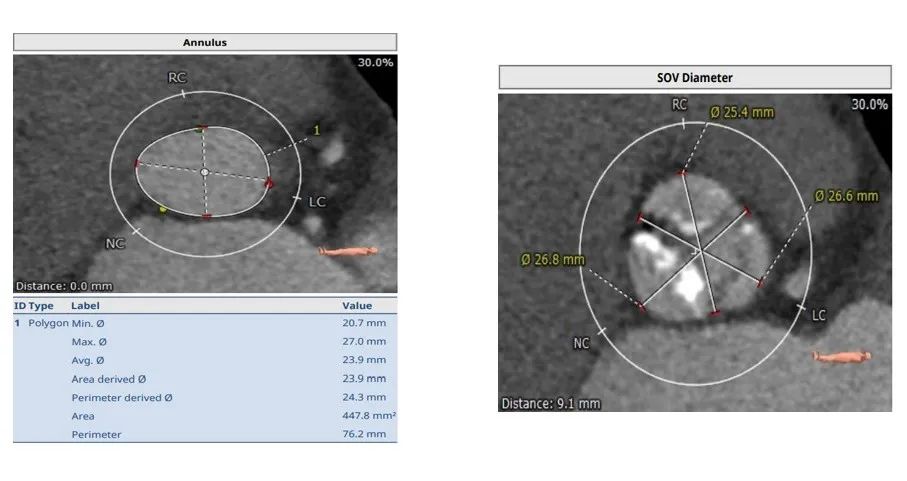

男性,85岁,术前超声提示EF 72%,Vmax=4.7m/s , 平均跨瓣压差51mmHg,重度主动脉瓣狭窄。

仔细分析对比完临床上常见的几款瓣膜系统后,最终团队决定选用SAPIEN 3瓣膜。首先是因为SAPIEN 3瓣膜系统所使用的输送鞘管是临床上常用瓣膜产品中最细的一款。其次,CT评估出患者冠脉开口处存在风险,球扩瓣也能帮助降低TAVR手术对冠脉开口的影响。